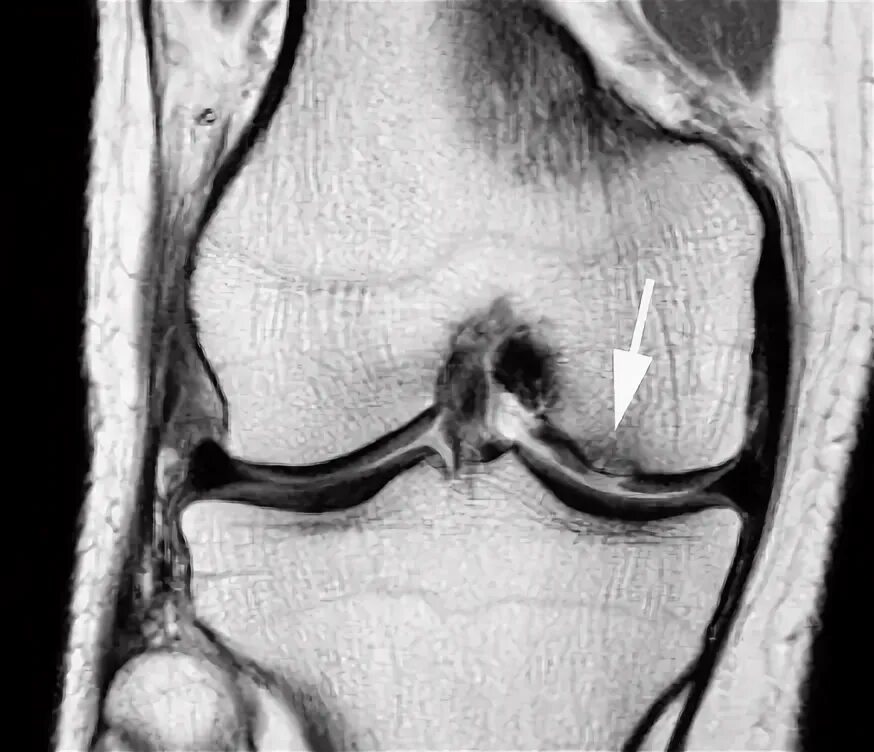

Мрт при боли в суставах